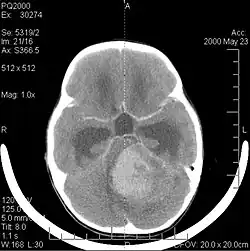

Billeddiagnostik

Computertomografi (CT) og magnetisk resonansbilleddannelse (MRI) kan effektivt påvise en neoplasi i hjernen. MR er mere følsom end CT til at identificere læsioner, men har kontraindikationer for patienter med pacemakere, inkompatible proteser, metalclips og andre. CT er fortsat den foretrukne metode til at påvise forkalkninger i læsioner eller knogleerosion af kaloten eller bunden . Brugen af kontrastmidler, som er ioderede i tilfælde af CT og paramagnetiske (gadolinium ) i tilfælde af MR, tillader erhvervelse af information om vaskularisering og integritet af blod-hjerne-barrieren, en bedre definition af den tumorøse tumor sammenlignet til det omgivende ødem og generering af hypoteser om graden af malignitet . Den radiologiske undersøgelse giver også mulighed for en vurdering af de mekaniske virkninger og deraf følgende ændringer i hjernestrukturer som følge af tumoren, såsom hydrocephalus og brok, hvis virkninger kan være dødelige. Til sidst, som forberedelse til operation, kan denne diagnostik bruges til at bestemme placeringen af læsionen eller infiltrationen af tumoren i vitale områder af hjernen. Til dette formål er MR mere effektiv end CT, fordi den kan give tredimensionelle billeder.

Diagnostiske radiologiske billeddannelsesværktøjer fremhæver ændringen i neoplastisk væv sammenlignet med normal hjerneparenkym (gennem ændringer i elektronisk afbildet vævstæthed på CT og signalintensitet på MR). Som de fleste patologiske væv er tumorer også genkendelige ved en øget ophobning af intracellulært vand. I computertomogrammet forekommer de hypodense, dvs. med mindre tæthed end hjerneparenkymet, i det nuklear magnetiske resonans tomogram med spin-gitter-relaksation hypointens og i spin-spin afslapning.

Computertomografi af hjernen viser typisk en vævsmasse, der kan forstærkes af begge kontraster. På CT forekommer lavgradige gliomer sædvanligvis isodense til det normale parenkym og viser derfor muligvis ikke kontrastforstærkning. På samme måde er læsioner i den bagerste kraniale fossa svære at identificere på CT. Følgelig er resultaterne af en sådan tomografi alene ikke altid tilstrækkelige til diagnostiske formål. I tvivlstilfælde er brugen af den mere følsomme magnetiske resonansbilleddannelse afgørende.